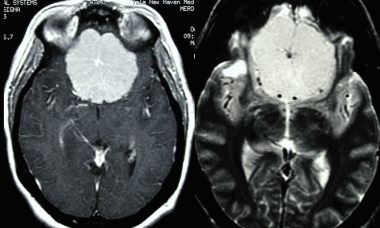

(а) Бесконтрастная КТ, аксиальный срез: у мужчины 33 лет с длительным анамнезом судорожных приступов в верхне-задней части правой теменной доли визуализируется кальцифицированное объемное образование, повторяющее ход извилин.

(б) MPT, FLAIR, аксиальный срез: у того же пациента в структуре коры визуализируется гипоинтенсивное объемное образование.

2. КТ при менингоангиоматозе:

• Бесконтрастная КТ:

о Одиночное гиперденсное, часто кальцифицированное объемное образование:

- Линейный, гиральный или узловой характер Са++

о Обнаруживаются случайно: кровоизлияния и кисты

о Масс-эффект отсутствует или не определяется

• КТ с контрастированием:

о Контрастирование низкоинтенсивное или отсутствует

(а) MPT, Т2* GRE, аксиальный срез: определяются участки «выцветания» изображения, соответствующие участкам кальцификации гирального характера.

(б) Постконтратсное Т1-ВИ, режим подавления сигнала от жира, аксиальный срез: определяется контрастное усиление объемного образования серпантинного, гирального характера.

Других областей поражения или кожных аномалий выявлено не было. На данных снимках представлен случай предполагаемого (хирургически не подтвержденного) менингоангиоматоза.